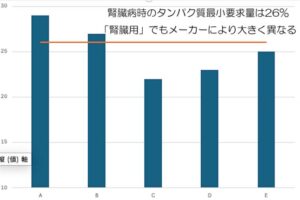

🐾3月12日は「世界腎臓デー(World Kidney Day)」でした